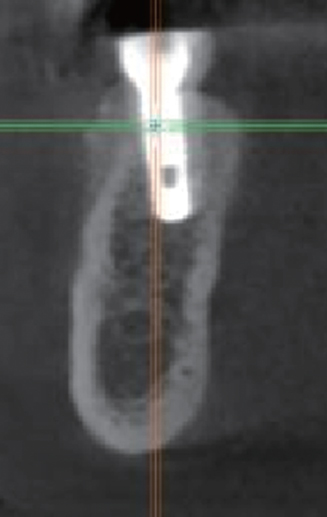

#45 Implant 식립

#47 Implant 식립

수술 후 파노라마